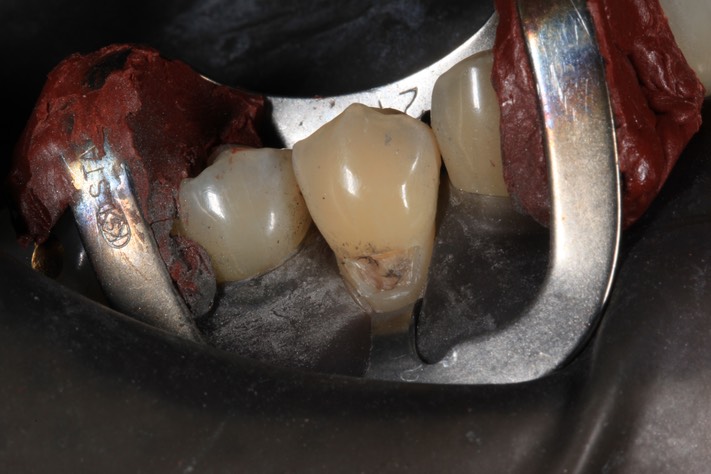

Gary Umeda #28 amalgam removal